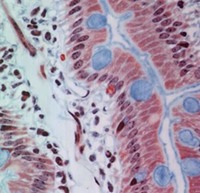

Simple Columnar Epithelium

Pseudostratified columnar epithelium